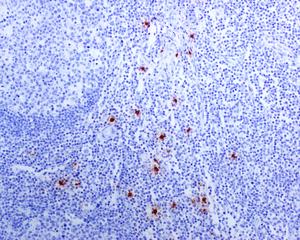

Immunohistochemistry (Formalin/PFA-fixed paraffin-embedded sections) - Anti-Mast Cell Tryptase antibody [EPR8476] - BSA and Azide free (AB227572)

This IHC data was generated using the same anti-Mast Cell Tryptase antibody clone, EPR8476, in a different buffer formulation (cat# ab134932).

Immunohistochemical analysis of paraffin-embedded, formalin-fixed Human tonsil tissue, labelling Mast Cell Tryptase using ab134932 at a 1/500 dilution.

Heat mediated antigen retrieval was performed with citrate buffer pH 6 before commencing with IHC staining protocol.